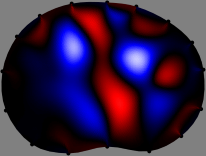

Figs. 3 and 4 compare the performance of the proposed FER method in (20) with the standard regularized least-squares method ((19) when is the identity matrix). The regularization parameter of the standard method was heuristically chosen for its best performance, and the parameter of the FER method was set to be one of three different values . The injection current was 1 mA at 100 kHz, and the frame rate was 9 frames per second. The reference frame at was obtained from the maximum expiration state. The measured data, , represent the voltage differences between each time and . The blue regions, which denote where conductivity decreased by inhaled air, increased during inspiration and decreased during expiration. The FER method with was clearly more robust than the standard method that produced more artifacts originated from the inversion process.

| Standard | |

||||||||||

| FER () | |

| FER () | |||||||||||